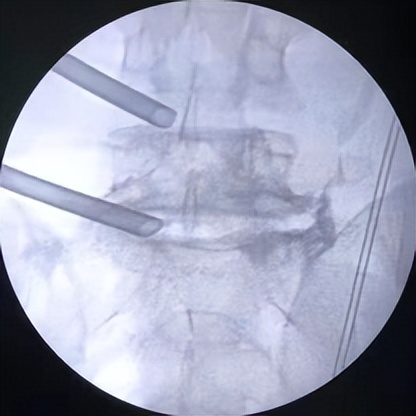

微创椎间孔镜术中